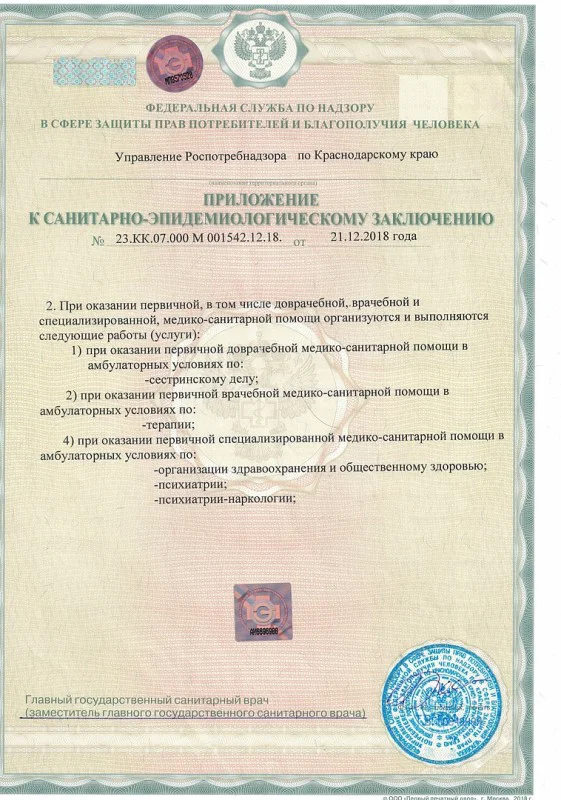

Лицензия на осуществление медицинской деятельности

Лицензия на осуществление медицинской деятельности

Лицензия на осуществление медицинской деятельности

Лицензия на осуществление медицинской деятельности

Лицензия на осуществление медицинской деятельности

Лицензия на осуществление медицинской деятельности

Лицензия на осуществление медицинской деятельности

Лицензия на осуществление медицинской деятельности